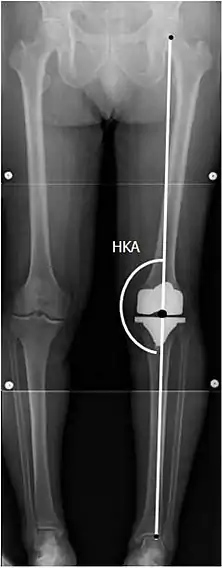

To indicate knee replacement in case of osteoarthritis, its radiographic classification and severity of symptoms both should be substantial. Such radiography should consist of weightbearing X-rays of both knees: AP, lateral, and 30 degrees of flexion. AP and lateral views may not show joint space narrowing, but the 30-degree flexion view is most sensitive for narrowing. Full-length projections also are used in order to adjust the prosthesis to provide a neutral angle for the distal lower extremity. Two angles used for this purpose are:

- Hip-knee-shaft angle (HKS),[10] an angle formed between a line through the longitudinal axis of the femoral shaft and its mechanical axis, which is a line from the center of the femoral head to the intercondylar notch of the distal femur.[12]

- Hip-knee-ankle angle (HKA),[11] which is an angle between the femoral mechanical axis and the center of the ankle joint.[12] It is normally between 1.0° and 1.5° of varus in adults.[13]